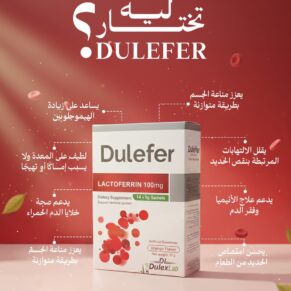

⚠️ ملاحظات هامة قبل استخدام الزيوت الطبيعية والمكملات الغذائية في السنوات الأخيرة، اتجه الكثير من الأشخاص لاستخدام الزيوت الطبيعية والمكملات الغذائية كجزء من نمط حياة صحي يدعم التوازن العام للجسم. ورغم الفوائد المحتملة لهذه المنتجات، إلا أن التعامل معها يحتاج إلى قدر من الوعي والمعرفة، لأن استجابة الجسم تختلف [...]